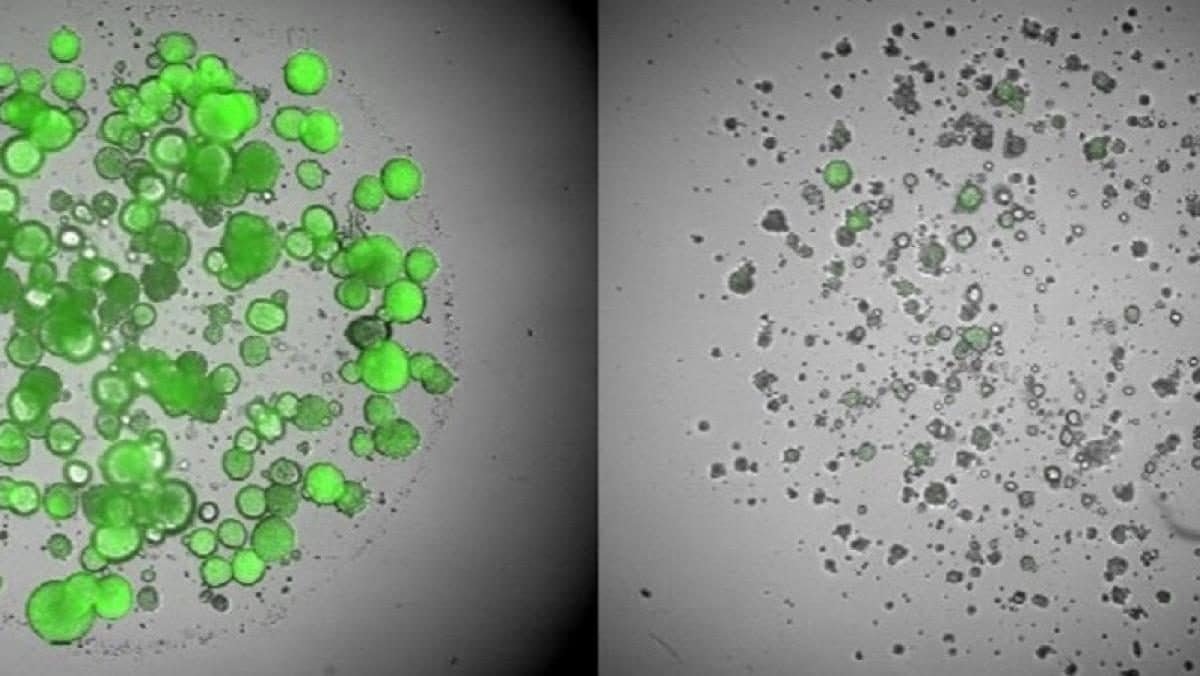

L’inquinamento dell’aria, all’esterno e negli edifici, è collegato all’1% di tutti i casi di cancro in Europa e causa circa il 2% di tutte le morti per tumore. Solo per il cancro ai polmoni, la percentuale sale al 9% delle morti. L’esposizione al radon è legata al 2% di tutti i casi di tumore, e la radiazione ultravioletta naturale al 4%, specie per il melanoma.

Il fumo passivo può aumentare il rischio di cancro fino al 16% in persone che non hanno mai fumato. Alcune sostanze chimiche usate nei luoghi di lavoro in Europa e rilasciate nell’ambiente sono cangerogene: piombo, arsenico, cromo, cadmio, acrylamide, pesticidi, Bisfenolo A e Pfas. L’amianto provoca dal 55 all’88% dei casi di tumore al polmone sul posti di lavoro, oltre a colpire laringe e ovaie.